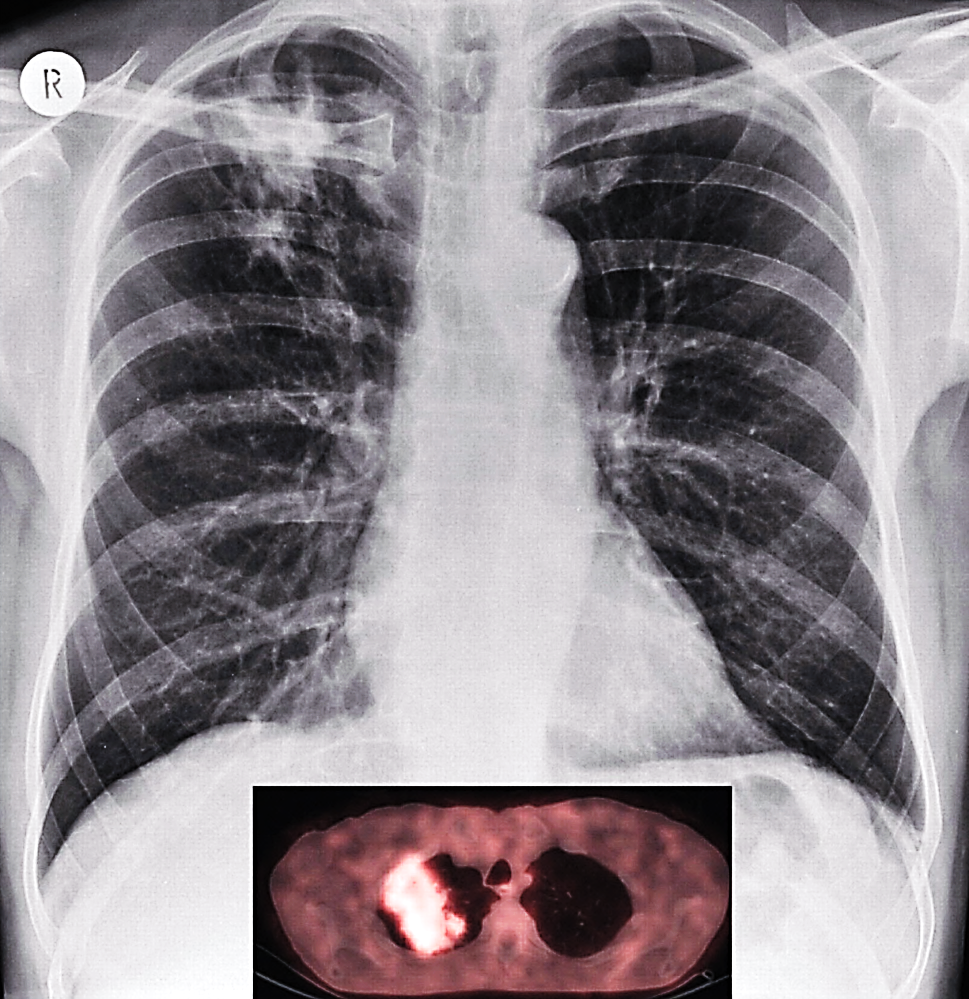

Unlike the situation in well-resourced health systems, it may not always be possible for treatment to be protocol-driven as the majority of patients are dependent on state run services with poor health infrastructure and resources. For the same reasons protocols designed for developed world settings are not always relevant; e.g.tuberculosis mimics metastases on PET scan, therefore limiting its utility as a staging tool in societies where tuberculosis is endemic (Figure 8).